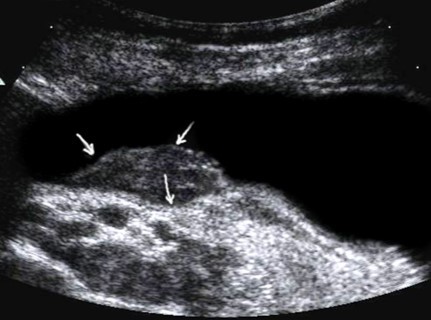

Metastasis to the regional lymph nodes was diagnosed in 52 cases. Ultrasonographically, this was detected in 37 (71.2%) cases. Sonographic features of lymph node metastatic lesions are: an increase in their thickness, a decrease in echogenicity, deterioration or lack of differentiation of the peripheral and central parts of the nodes, recording of color vascular signals inside the nodes (Figure 18, Figure 19).

Figure 18.Metastasis to the retroperitoneal lymph node in gastric cancer of the antrum of T3 stage. The longitudinal size of the lymph node is increased to 5 cm, the echo is significantly reduced, along the periphery of it is visible color vascular signals in tissue Doppler mode.